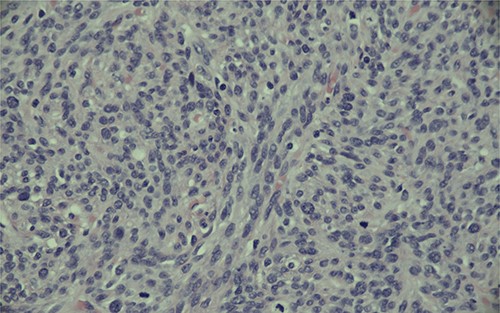

Magnification (400x) of histologic section of prostate, showing stromal sarcoma with moderate cytologic atypia and brisk mitotic activity.